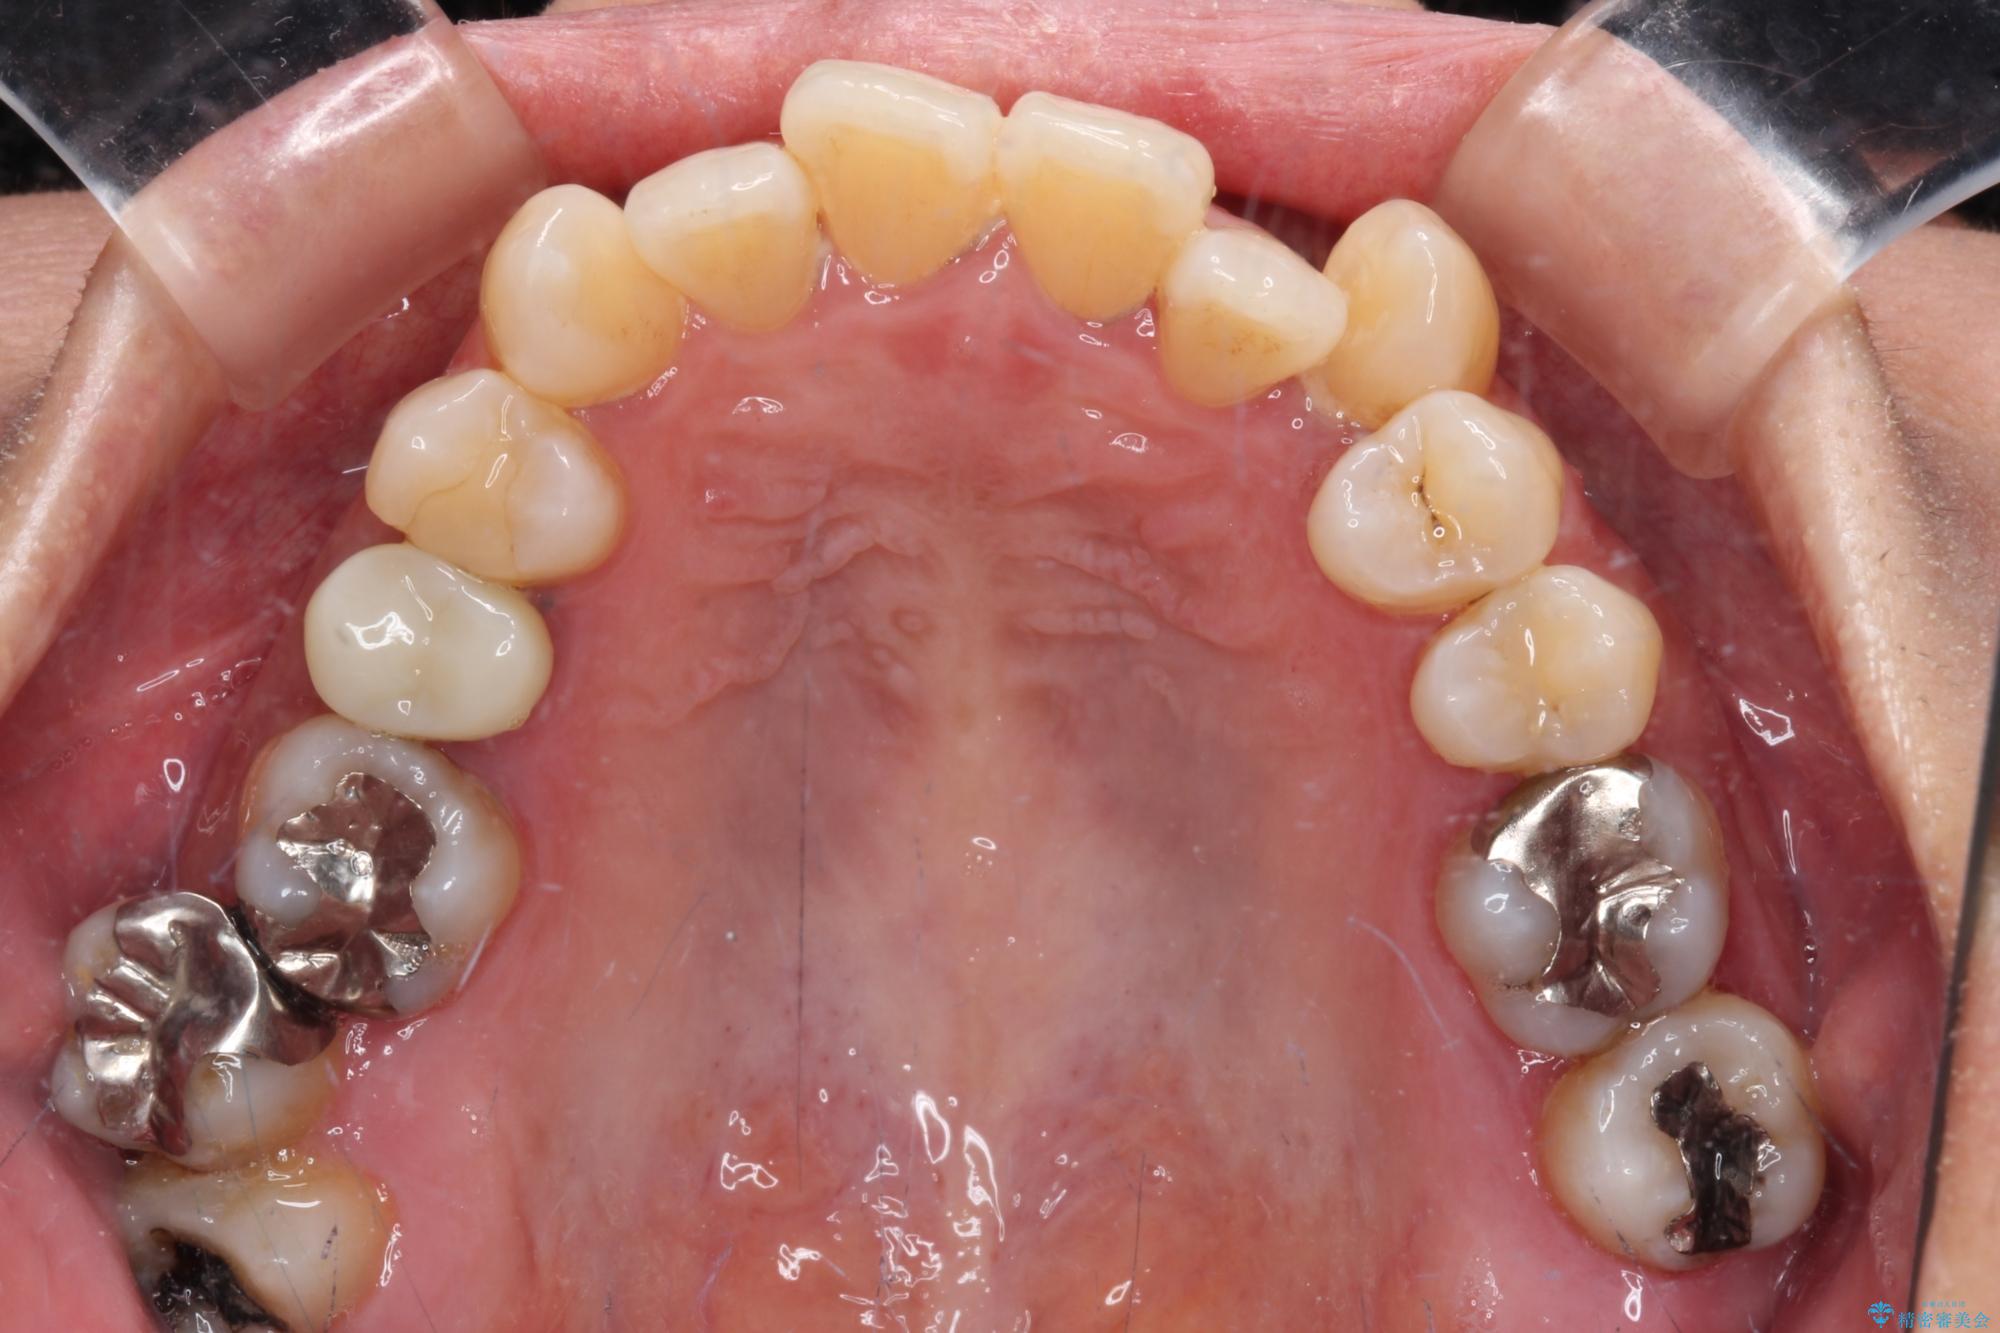

受け口と八重歯を改善 インビザライン矯正治療

- 前歯のデコボコや八重歯を治したいとのことで来院された患者様です。

受け口傾向の骨格であり、前歯はクロスバイトまたは切端咬合となっており、下顎を中心に歯列全体の後方移動を行い、IPR(歯と歯の間を削る)によってデコボコが解消するように設計し、インビザラインにより治療を行うこととしました。

受け口傾向のインビザライン矯正は比較的治療を行いやすいため、きれいに仕上げることができました。舌の突出癖が顕著であったため、改善のためのトレーニングをしっかりと行っていただきました。